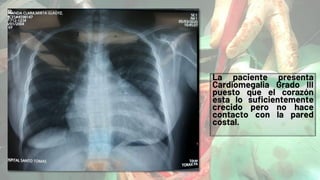

La paciente presenta

Cardiomegalia Grado III

puesto que el corazón

esta lo suficientemente

crecido pero no hace

contacto con la pared

costal.